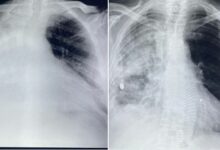

Alla Gepos intervento chirurgico straordinario salva la vita ad un paziente metastatico

Straordinario intervento salvavita eseguito alla Gepos di Telese Terme grazie alla equipe del chirurgo toracico, Alfonso Maiorino. Il paziente, già dimesso altrove, era giunto alla osservazione del chirurgo con una situazione...